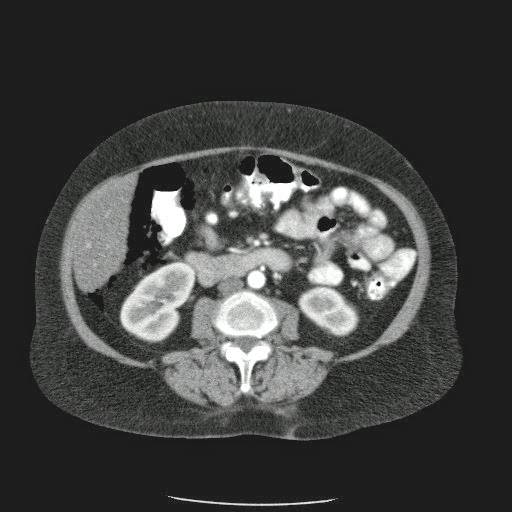

Caso Interesante #4

Adulto masculino, 1 semana de fiebre y malestar general.

¿Dónde esta ubicado el hallazgo?